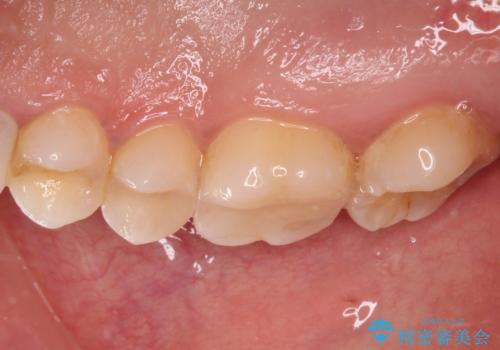

奥歯は抜歯をせずに保存することができました。ただし、状態は決して良いとは言えないため、定期的に経過を見ていく必要があります。